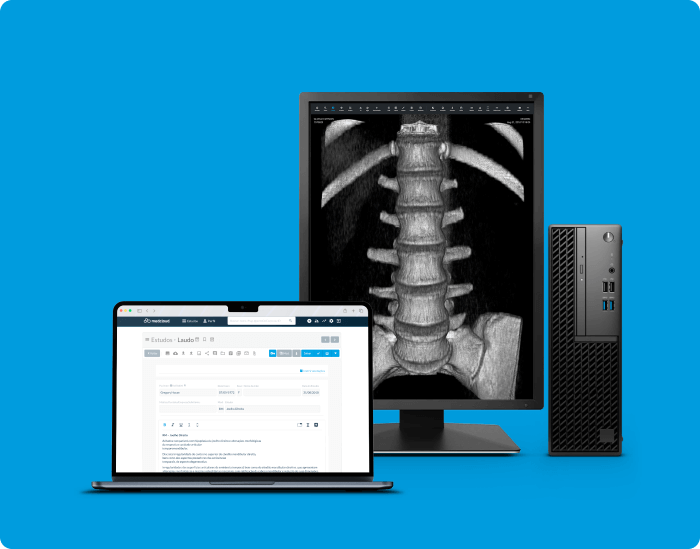

Accede a los exámenes desde tu computadora de escritorio o usando tu computadora portátil dondequiera que estés. Acceda a informes, archivos adjuntos e imágenes en calidad original, además de todas las herramientas que necesita, dondequiera que vaya.

Calidad diagnóstica en cualquier lugar, en cualquier momento y en el menor tiempo posible.

Calidad diagnóstica en cualquier lugar, en cualquier momento y en el menor tiempo posible.